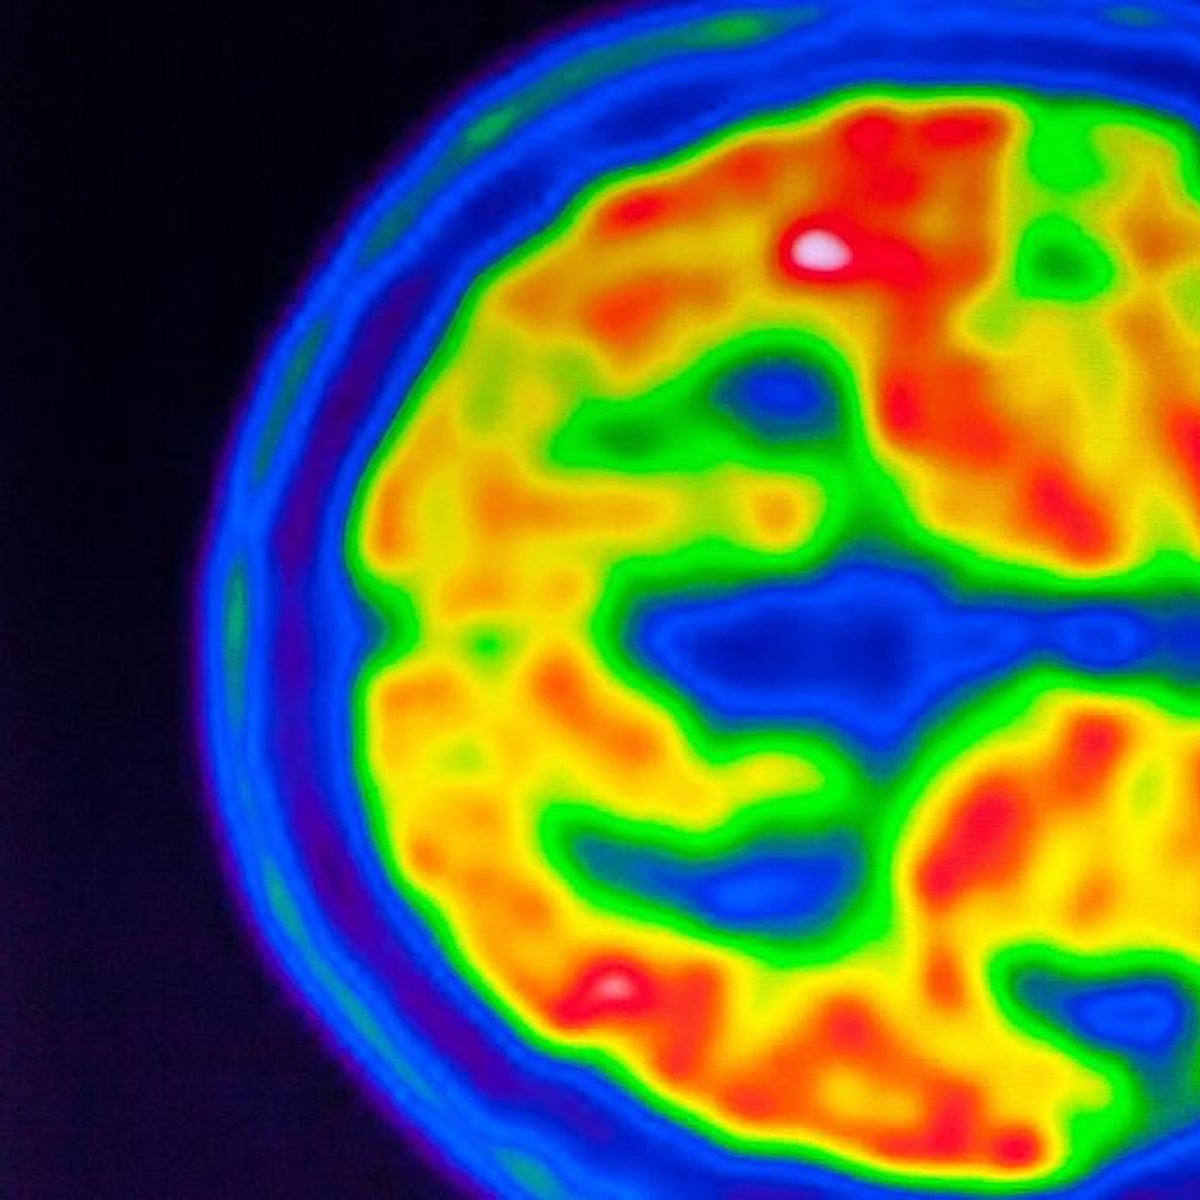

El nuevo tratamiento es un anticuerpo monoclonal que se administra como una infusión intravenosa cada dos semanas con el objetivo de limpiar las placas beta amiloide que se acumulan en el cerebro, una proteína tóxica vinculada a la enfermedad de Alzheimer.